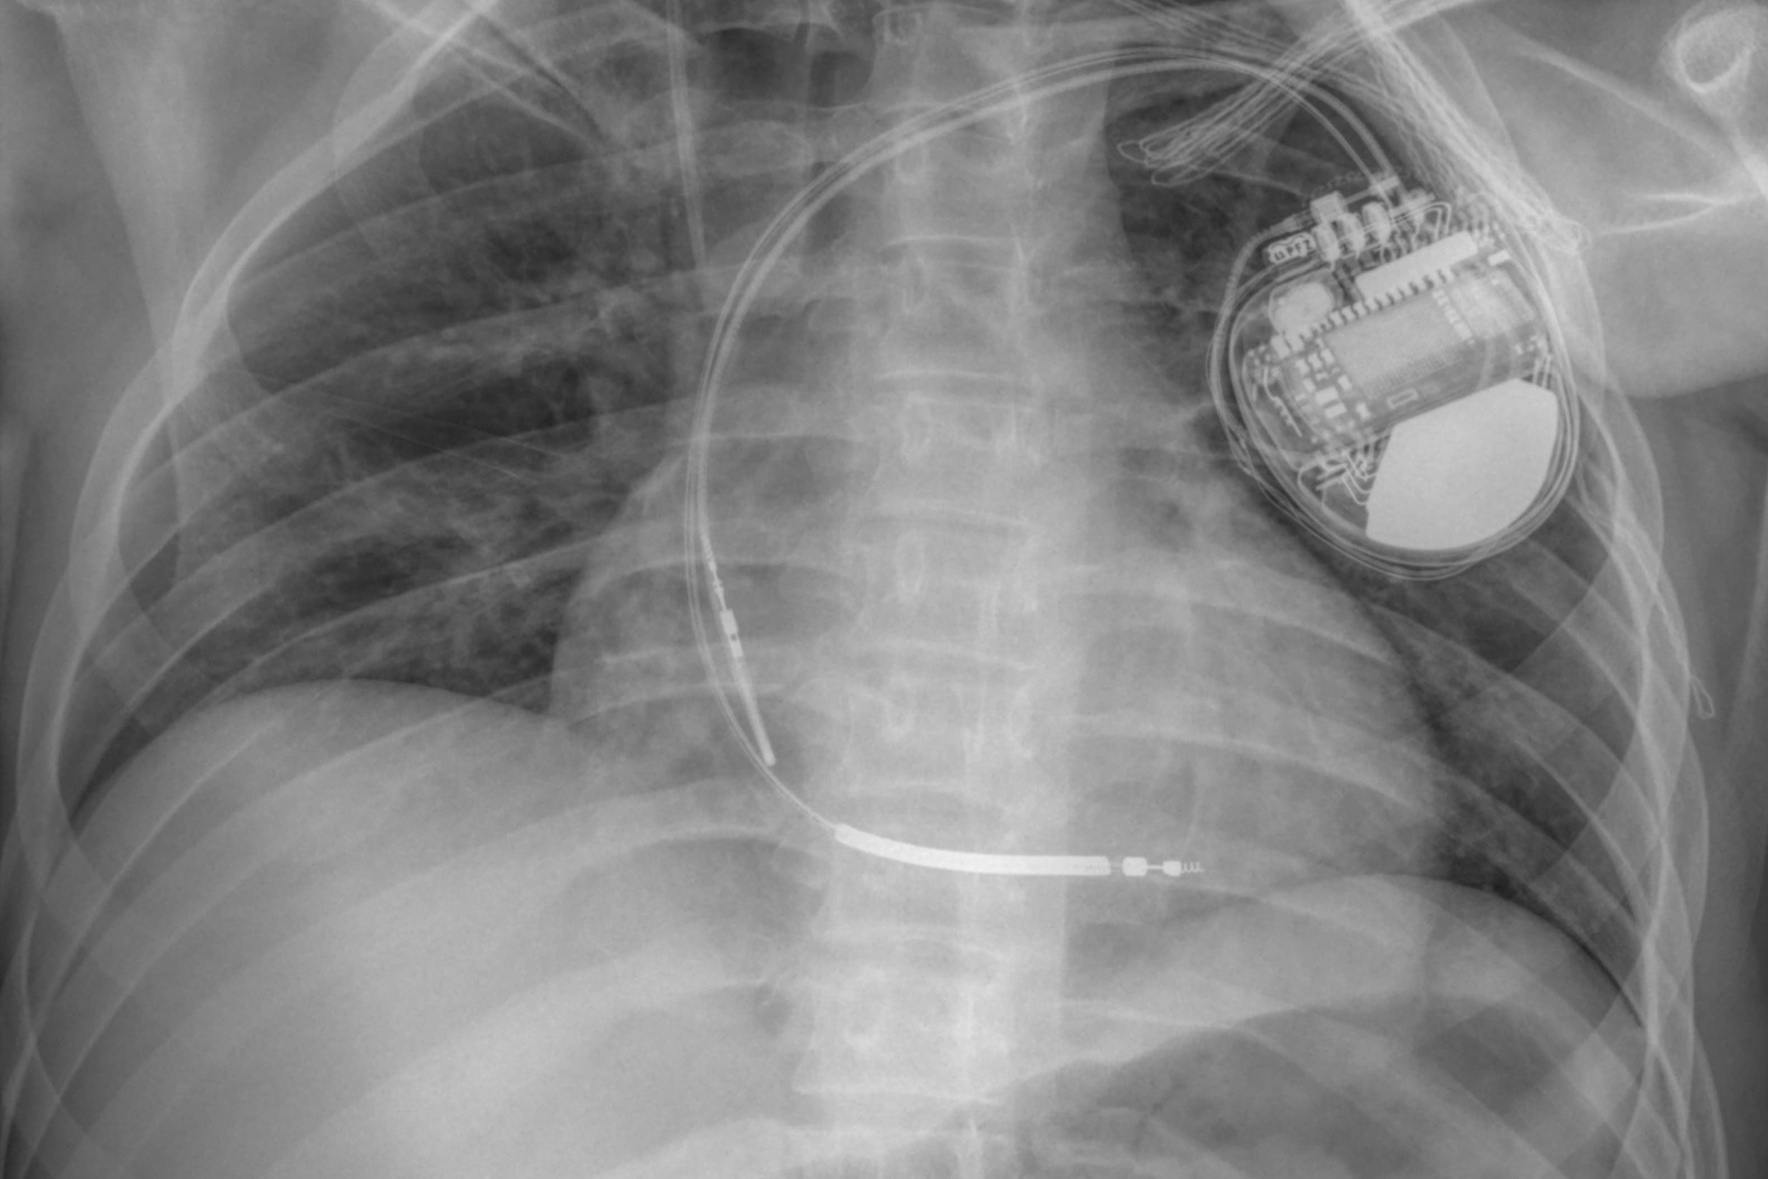

Amikor sikeresen elindult a rekuperáció útján, akkor a kardiológiai osztály munkatársai kezdtek el dolgozni azért, hogy a fiatalember ismét teljes életet élhessen: érfestést végeztek, majd egy defibrillátort ültettek be a szívébe. Kórházi tartózkodása alatt pszichológiai támogatást is kapott.

Az egyik környékbeli községből származó fiatal jelenleg jól van, jól mozog, nemrég vett részt felülvizsgálaton. Lesznek még vizsgálatok a vélhetően genetikai eredetű szívrendellenessége hátterének a feltérképezésére, az esetleges újabb rosszullétek esetén viszont megvédi a defibrillátor.